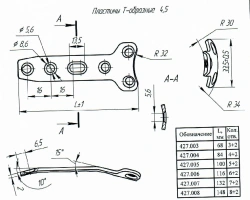

ألواح علوية جانبية من الساق 4.5 لتثبيت الكسور (424.013R/L)

لوحات على شكل T 4.5، المادة 427.004